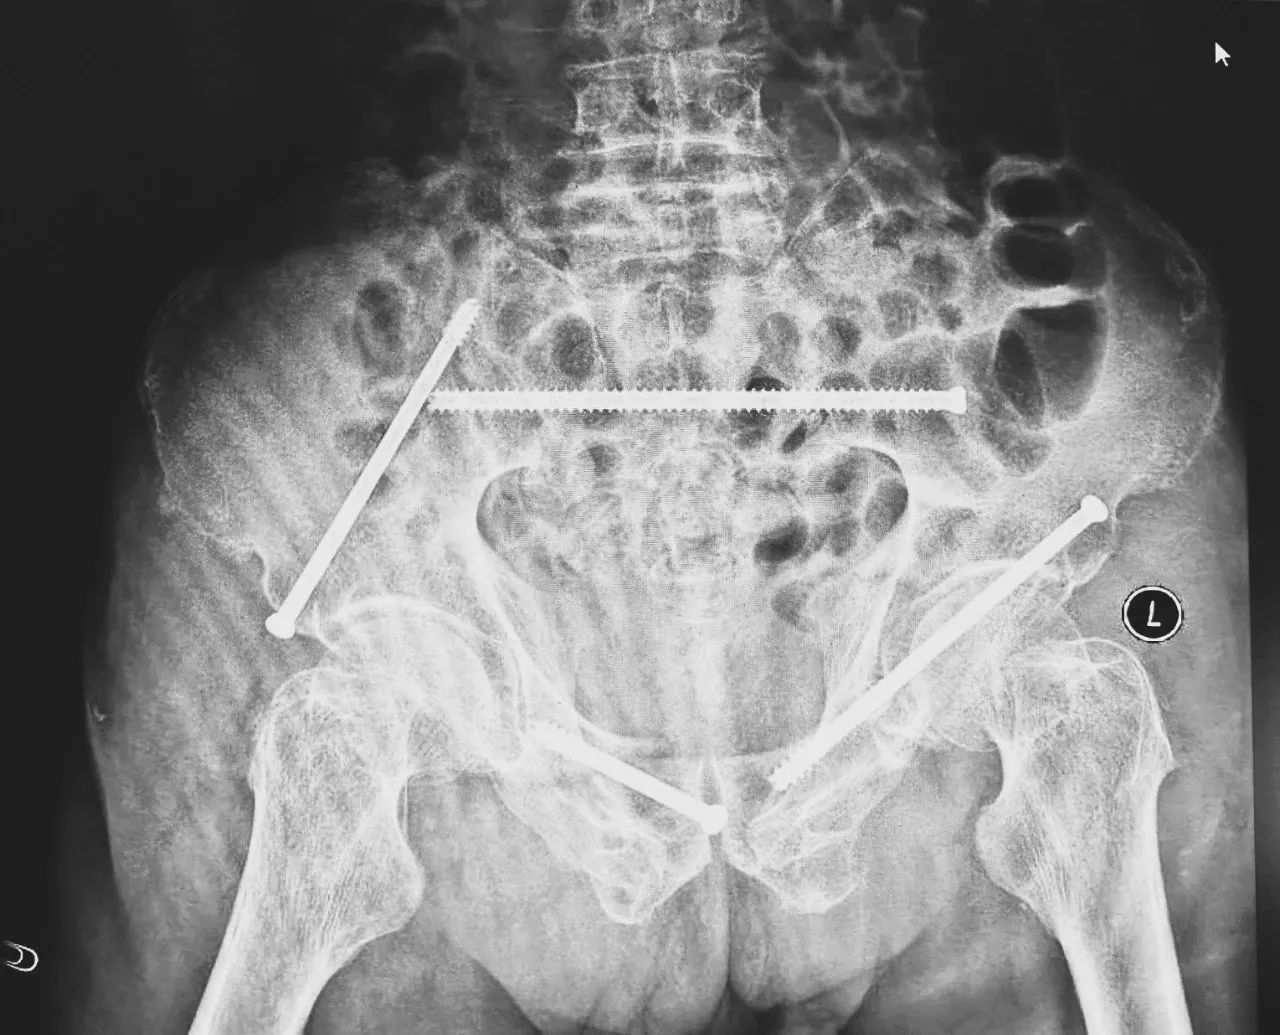

ÎÞÓ°µÆÏ£¬ÖÇÄܹǿÆÍŶӽ«»¼Õßʾ×ÙÆ÷£¬·ÅÔÚ×ó²à÷ÄǰÉϼ¬£¬Ê¹ÓÃÊõÖÐÈýάӰÏñ×°±¸»ñÈ¡¹ÇÅèµÄÈýάͼÏñ£¬É¨ÃèЧ¹û´«ÊäÖÁ»úеÈ˵¼º½ÏµÍ³£¬Íê³ÉÂݶ¤ÖÃÈëµÄλÖúÍ×ßÐΣ¬²¢ÔÚ»úеÈ˵ÄÖ¸µ¼Ï»®·ÖÖÃÈë4öͨµÀÂݶ¤¡£ÖÃÈëºóÔٴξÙÐÐCTɨÃèÑéÖ¤£¬Ö¤Êµµ¼Õë׼ȷÖÃÈë¡£

ÔڹǿÆÊÖÊõ»úеÈ˺ÁÃ×¼¶¾«¶ÈµÄÖ¸µ¼Ï£¬ÕâÏîÔ±¾¸ßÄѶȡ¢¸ßΣº¦µÄÊÖÊõ±äµÃÔ½·¢¾«×¼¸ßЧ¡£ÊÖÊõ¹²¼ÆºÄʱ1¸ö°ëСʱ£¬ÊõÖгöѪ²»µ½20ºÁÉý£¬Ã¿Ã¶Âݶ¤ÖÃÈëλÖõÄÇпڳ¤¶ÈÔ¼1.5ÀåÃ×£¬ÍêÉÆµÖ´ïÁËÔ¤ÆÚ¡£Êõºó£¬Íõ´óÒ¯Çå¾²·µ»Ø²¡·¿¡£

ÊõºóµÚ¶þÌ죬ҽÉúÍŶӸ´²éXƬÏÔʾÂݶ¤Ö²ÈëλÖúÜÊÇÖª×㣬¹ÇÕÛ»ù±¾µÖ´ïÎȹ̸´Î»£¬Í¬Ê±£¬¸´²éµÄȫѪϸ°û¼ÆÊýÖУ¬ÑªºìÂѰ×Ö¸ÊýΪ102g/L¡£ÊõºóµÚÈýÌ죬ÔÚÖÇÄܹǿƲ¡·¿Õչ˻¤Ê¿ÍŶӼ°¿µ¸´Ê¦µÄÖ¸µ¼ºÍÕչ˻¤Ê¿Ï£¬Íõ´óÒ¯¿ÉÒÔ×øÁ¢ÔÚ´²ÉÏ¡£ÊõºóµÚËÄÌ죬Íõ´óÒ¯ÓÀ´Á˳öÔºÈÕ£¬¡°µÃ¿÷ÓÐÁËÕâôÏȽøµÄÒ½ÁÆÊÖÒÕ£¬ÈÃÎÒ»¹ÄÜϵØÐÐ×ߣ¬Ð»Ð»ÄãÃÇ£¡¡±

Âݶ¤Ö²ÈëλÖúÜÊÇÖª×ã